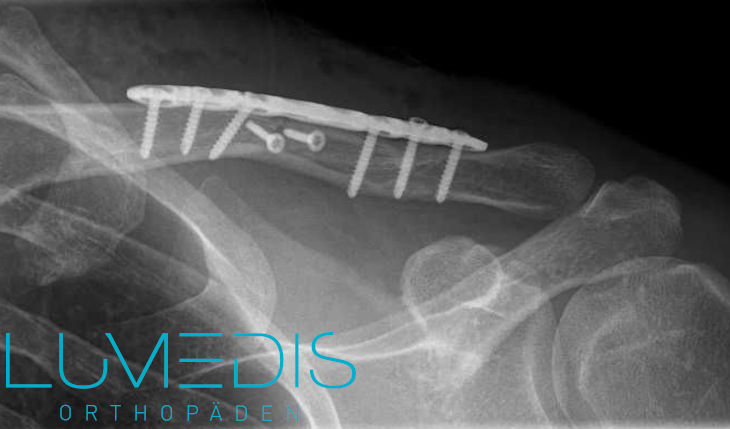

Schlüsselbeinbruch nach OP mit Platte und Schreiben

Röntgenbild eines gebrochenen Schlüsselbeins nach OP mit Platte und Schrauben

Bei einer notwendigen Operation im Rahmen eines Schlüsselbeinbruchs können verschiedene Techniken eingesetzt werden.

Zu den häufigsten gehört das Einbringen eines oder mehrerer Schrauben und einer Platte.

Es gibt hier wiederum verschiedene Platten wie 1/3 Rohrplatte oder Hakenplatte, die verwendet werden können.

Dabei ist der notwendige Hautschnitt zum Einbringen entgegen der Erwartungen meist nicht so groß und das kosmetische Ergebnis in der Regel sehr gut.

Meist wird eine Platte mit der Länge von 6 bis 10 Zentimetern eingebracht und mit Hilfe von kleinen Schrauben an den beiden Knochenstücken befestigt.

Der Einsatz einer Platte bei einem Schlüsselbeinbruch wird vor allem bei komplizierten Brüchen der Knochenmitte oder Knochenbrüchen im Bereich der Schulter genutzt.

Nach dem Einsatz einer Platte im Rahmen eines operativen Verfahrens sollte diese mindestens für drei Monate verbleiben, um ein optimales Wiederannähern der beiden Knochenstücke des Schlüsselbeins zu gewährleisten.

Das Entfernen der Platte ist in den meisten Fällen allerdings nicht notwendig, da hierdurch keine Nachteile für den Patienten entstehen. Eine Ausnahme bietet die sogenannte Hakenplatte, die als spezielle Form der operativ eingesetzten Platte nach drei Monaten meist wieder entfernt wird.